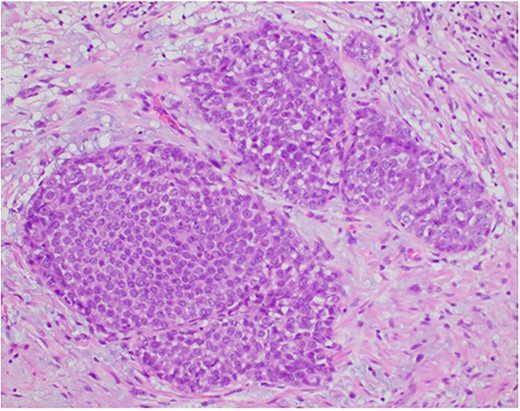

Photomicrograph showing the expanded ducts by classic lobular carcinoma in situ. (HE, ×200).

Photomicrograph showing a few ducts within the fibroadenoma expanded by a monotonous epithelial proliferation of classic lobular carcinoma in situ (arrows). (HE, ×20).